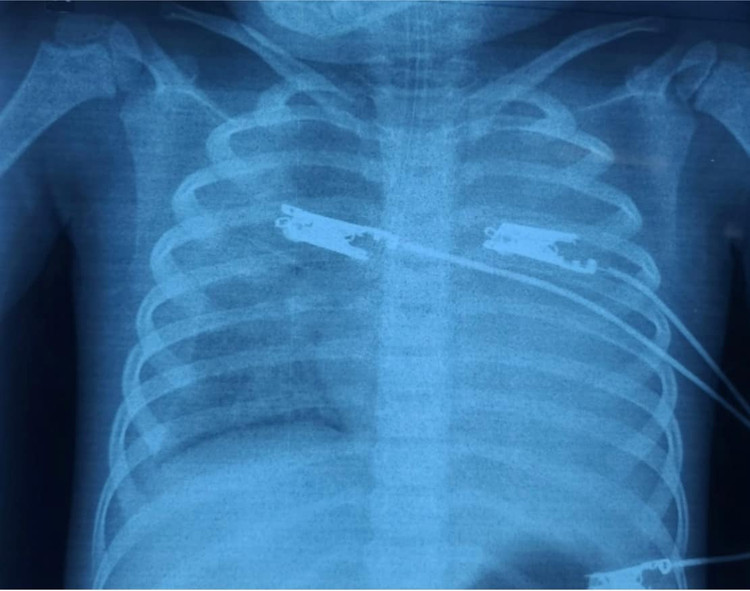

Bệnh sử cho thấy bé 4 ngày đầu sốt nhẹ, chán ăn, ngày 5 và 6 sốt cao hơn, nôn ói , da xanh xao và đi tiểu sậm màu. Bé nhập viện trong tình trạng thiếu máu nặng (dung tích hồng cầu 16%), gan to 4 cm dưới hạ sườn phải và lách to độ 4; các xét nghiệm tại cấp cứu cho thấy nhiễm khuẩn nặng CRP 188 mg/L, Ferritin 4403,85 ug/L, lactate 4,3 mmol/l; tổn thương phổi và tràn dịch màng phổi phải.

Diễn tiến bé sốt cao kéo dài, tổn thương gan và thận nặng (men gan > 1000 UI/L), phản ứng viêm còn rất cao LDH: 2314.9 U/L, Ferritin: 10951 ug/L, đông máu nội mạch lan toả với D-Dimer > 20 ug/ml và tiểu cầu giảm 31.000/mm3; tổn thương phổi với hội chứng nguy kịch hô hấp cấp do viêm lan toả 2 phổi, tuỷ đồ có hình ảnh thực bào máu.

![]() |

| Tổn thương phổi dẫn tới suy hô hấp |